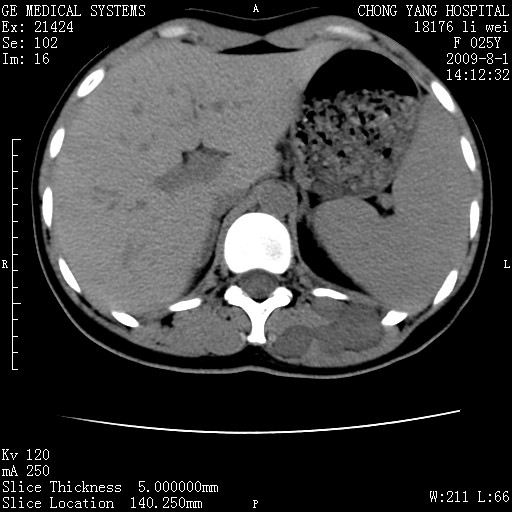

以下是引用pujunzhi在2009-8-1 20:23:00的发言:[br]胸椎旁及背部肌间良性病变,范围广,边界清,沿肌间生长,考虑淋巴管瘤、血管瘤,建议增强扫描。